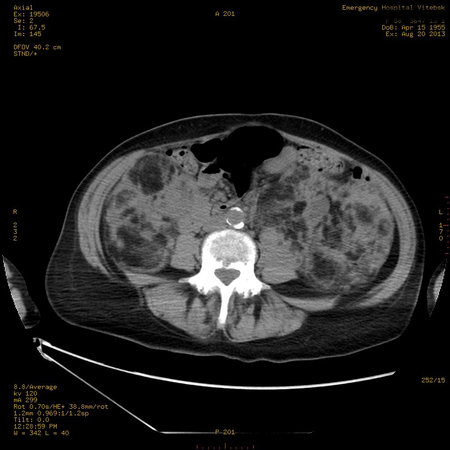

Пожилая женщина с нормальными мочевиной и креатинином.

Ангиомиолипоматоз почек , думаю компонент туберозного склероза.

Да, туберозный склероз.

Случай консультирован на кафедре радиологии Католического университета г.Лёвен (Бельгия) - зав каф. профессор Р.Оуен.